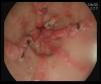

Ingresa por episodio de melenas con datos de anemización, al realizar exploración endoscópica se evidencian en antro lesiones de aspecto vascular, confluentes hacia el píloro, compatibles con estómago en watermelon1,2 (fig. 1). Ante la presencia de sangrado activo en sábana, se realiza tratamiento con argón3 (fig. 2).

La ectasia vascular gástrica antral (EVGA) constituye una causa rara, pero grave, de hemorragia gastrointestinal alta (4% de todas las hemorragias digestivas). Los hallazgos endoscópicos son característicos: imágenes lineales, orientadas en forma radial partiendo del píloro (imagen de estómago en sandía o watermelon stomach1,4).